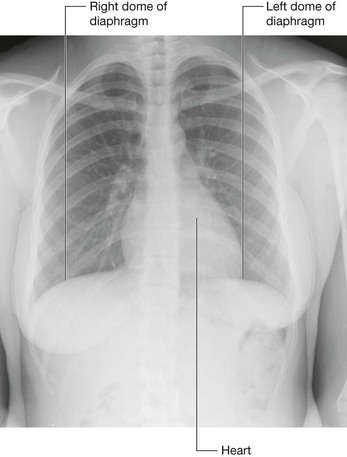

Domes

The classic appearance of the right and left domes of the diaphragm is caused by the underlying abdominal contents pushing these lateral areas upward, and by the fibrous pericardium, which is attached centrally, causing a flattening of the diaphragm in this area (Fig. 4.132).

Fig. 4.132 Right and left domes of the diaphragm. Chest radiograph.

The domes are produced by:

image the liver on the right, with some contribution from the right kidney and the right suprarenal gland; and

image the fundus of the stomach and spleen on the left, with contributions from the left kidney and the left suprarenal gland.

Although the height of these domes varies during breathing, a reasonable estimate in normal expiration places the left dome at the fifth intercostal space and the right dome at rib V. This is important to remember when percussing the thorax.